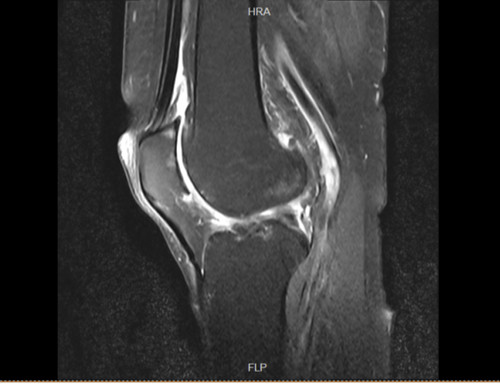

入院后,检查结果出来了,我的膝关节半月板撕裂、髌骨软化、韧带损伤、骨髓水肿,并且有大量积液。我先生的腰椎,包括整个脊柱都有问题,尤其是腰椎间盘突出压迫到坐骨神经,下肢麻木疼痛,让他苦不堪言。